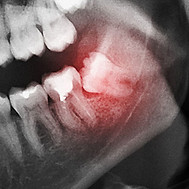

במידה ומדובר בשן בינה מסובכת לעקירה, כדאי לפנות למומחה לכירורגיית פה ולסת בעל כלים ונסיון בהתמודדות עם שיניים כאלו. בחלק מהמקרים לפני הטיפול יהיה צורך בבדיקה מקדימה וכמעט תמיד - בהדמיית רנטגן כלשהי, כמו צילום פנורמי.

לפני שניגשים לביצוע העקירה, הרופא יעריך את המצב בעזרת צילום פנורמי. לעיתים, הצילום יראה כי השן כלואה וסמוכה לתעלה בה עובר העצב המנדיבולרי. עצב זה אחראי על התחושה והשפה התחתונה, הסנטר והחניכיים באותו צד של הלסת.

לשם כך, יבקש הכירורג להתרשם מהאזור באופן מעמיק יותר באמצעות CT. זוהי טכנולוגיה נוספת להדמיית רנטגן שמספקת יותר מידע ו״מבט״ על האזור מכיוונים נוספים. השילוב של שני הצילומים יאפשר לכירורג להגיע להחלטה נכונה בנוגע לתכנית הטיפול שתאפשר את העקירה בצורה הנוחה והבטוחה ביותר.